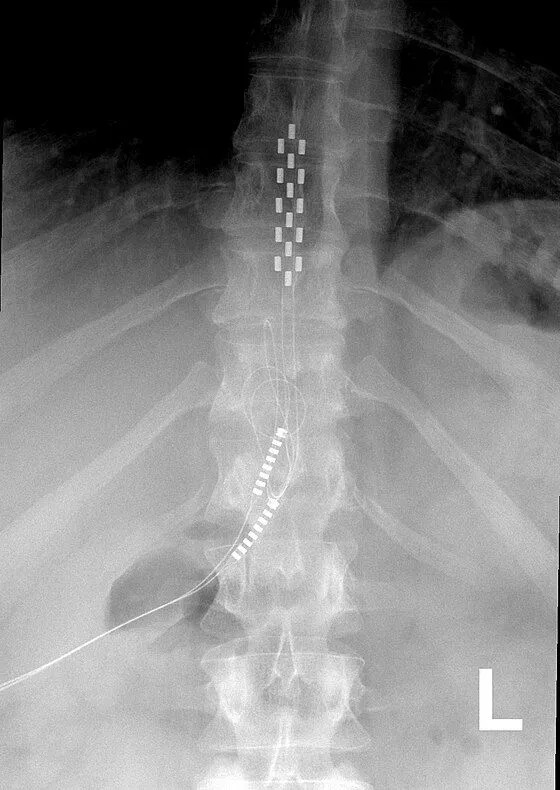

X-ray showing a spinal cord stimulator with leads along the spine.

Lead Migration & Scar Tissue

X-ray image showing a spinal column with a spinal cord stimulator implant.

Lead Migration

Implanted leads shift from their original position, causing loss of pain relief and requiring revision surgery.